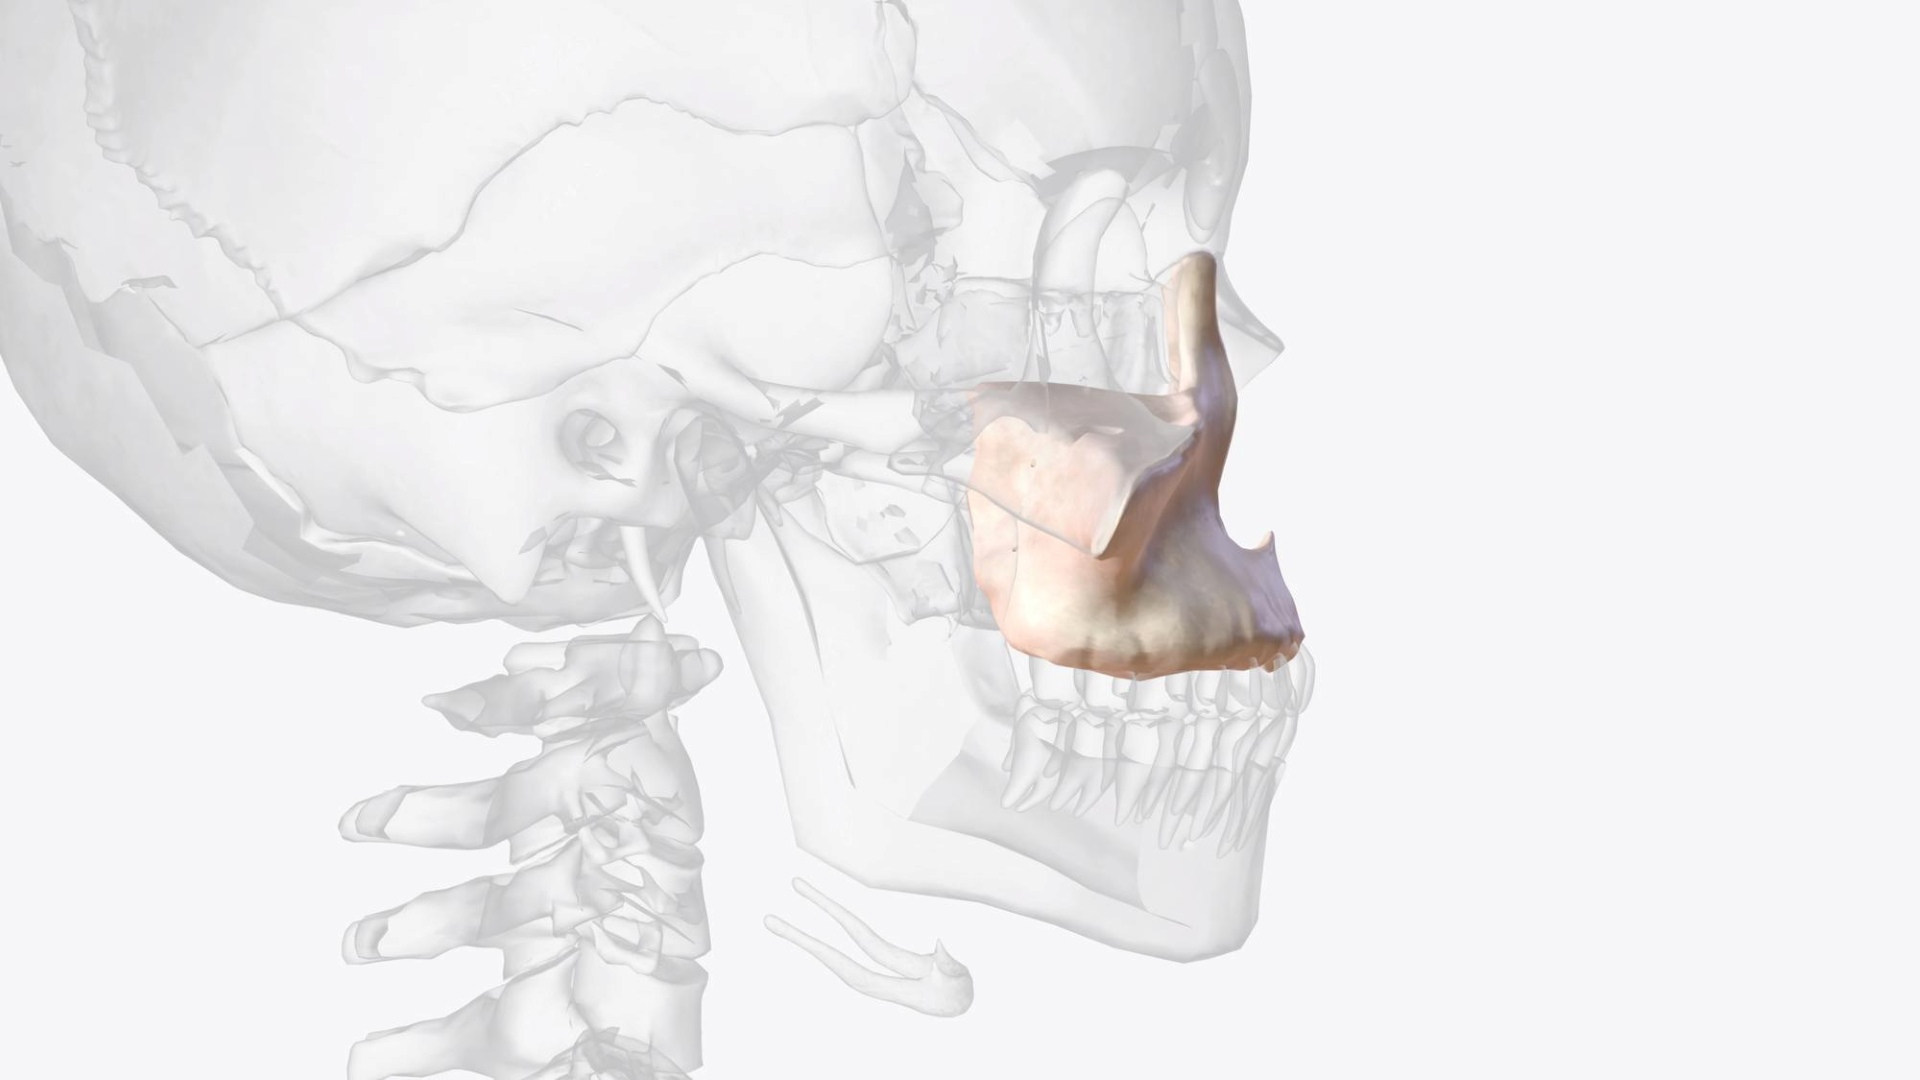

Upper Jawbone

Growth stop at ~8years old

Lower Jawbone

Peak growth (girl): ~12 years old

Peak growth (boy): ~14 years old

Case Study 2

Upper jaw growth → Corrected reverse bite

Age

9 years old

“Her lower jaw covering upper jaw, how can Dr help with this?”

Clinical observation

Upper jaw is under-developed.

Treatment Approach

Promote mid face growth (Clear Aligner + facemask)

Treatment simulation

*side view focus on the upper jaw advancement

Treatment Outcomes

Her reverse bite was corrected in just a few months! 😁